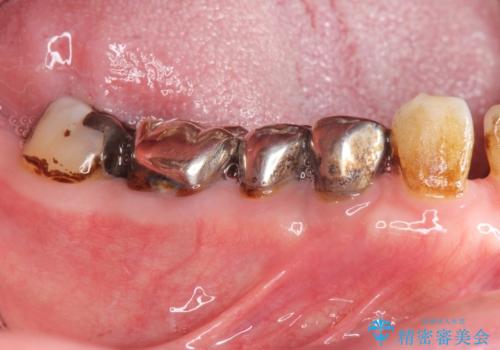

大臼歯 再根管治療

- 銀歯を白くしたいとの希望で来院されました。

せっかく銀歯を白くしても後々根管治療が必要になり、また壊して再治療を行うことを避けたいとの事でしたので、再根管治療から行っていきます。

ただ銀歯を白くするのではなく長期的な予後には歯の内部、根管治療の成功が必要不可欠です。